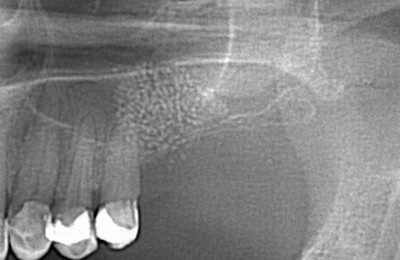

Гайморит может развиться также после лечения зубов. Когда оно заключается в рассверливании кариозных полостей и пломбировке, это случается, чаще всего, вследствие некачественной работы или халатности стоматолога.

Мембрана Шнайдера

Когда пломбировочный материал попадает в полость верхнечелюстного синуса непосредственно через просверленный корень, он становится инородным (т.е. чужеродным) телом, которое вызывает воспаление.

Во втором случае, когда происходит удаление нежизнеспособного зуба, корень может повредить мембрану Шнайдера и причина перфорации, в большей степени анатомически обусловлена. Воспаление вызывается нормальной микрофлорой полости рта.

После возможно осложнение – бактериальная инфекция и появление признаков острого гнойного гайморита.

Если пломбировочный материал в гайморовой пазухе — требуется немедленное хирургическое вмешательство. Любое инородное тело требует удаления. Производится операция по поводу экстракции пломбировочного материала из гайморовой пазухи, санация ее полости.

При подозрении на одонтогенный гайморит производится ряд диагностических исследований, в том числе и эндоскопия синуса, которая дает наглядную информацию о патологическом процессе в его полости.  В случае перфорации мембраны Шнайдера или подслизистой локализации воспалительного процесса врач увидит эти изменения.